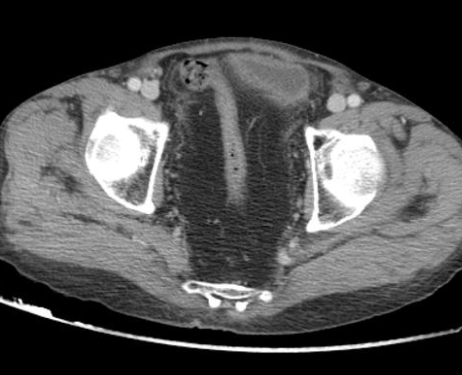

Lipofibromatose pelvienne

Général

• Excès de gras dans le pelvis

• Prédominant chez patients Noirs